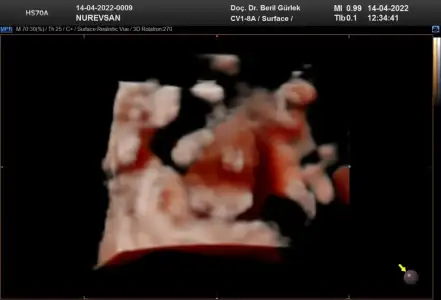

• IMG-20220414-WA0005.webp

IMG-20220414-WA0005.webp

15,8 KB · Görüntüleme: 80

Ay ne güzel başlık banada tahmın edebılır mısın😊🤗 burda 8 haftalık karından bakıldı sımdı 10 haftalıgım 2 hafta sonra gidicem doktora bır tahmınde bulınabılır mısın